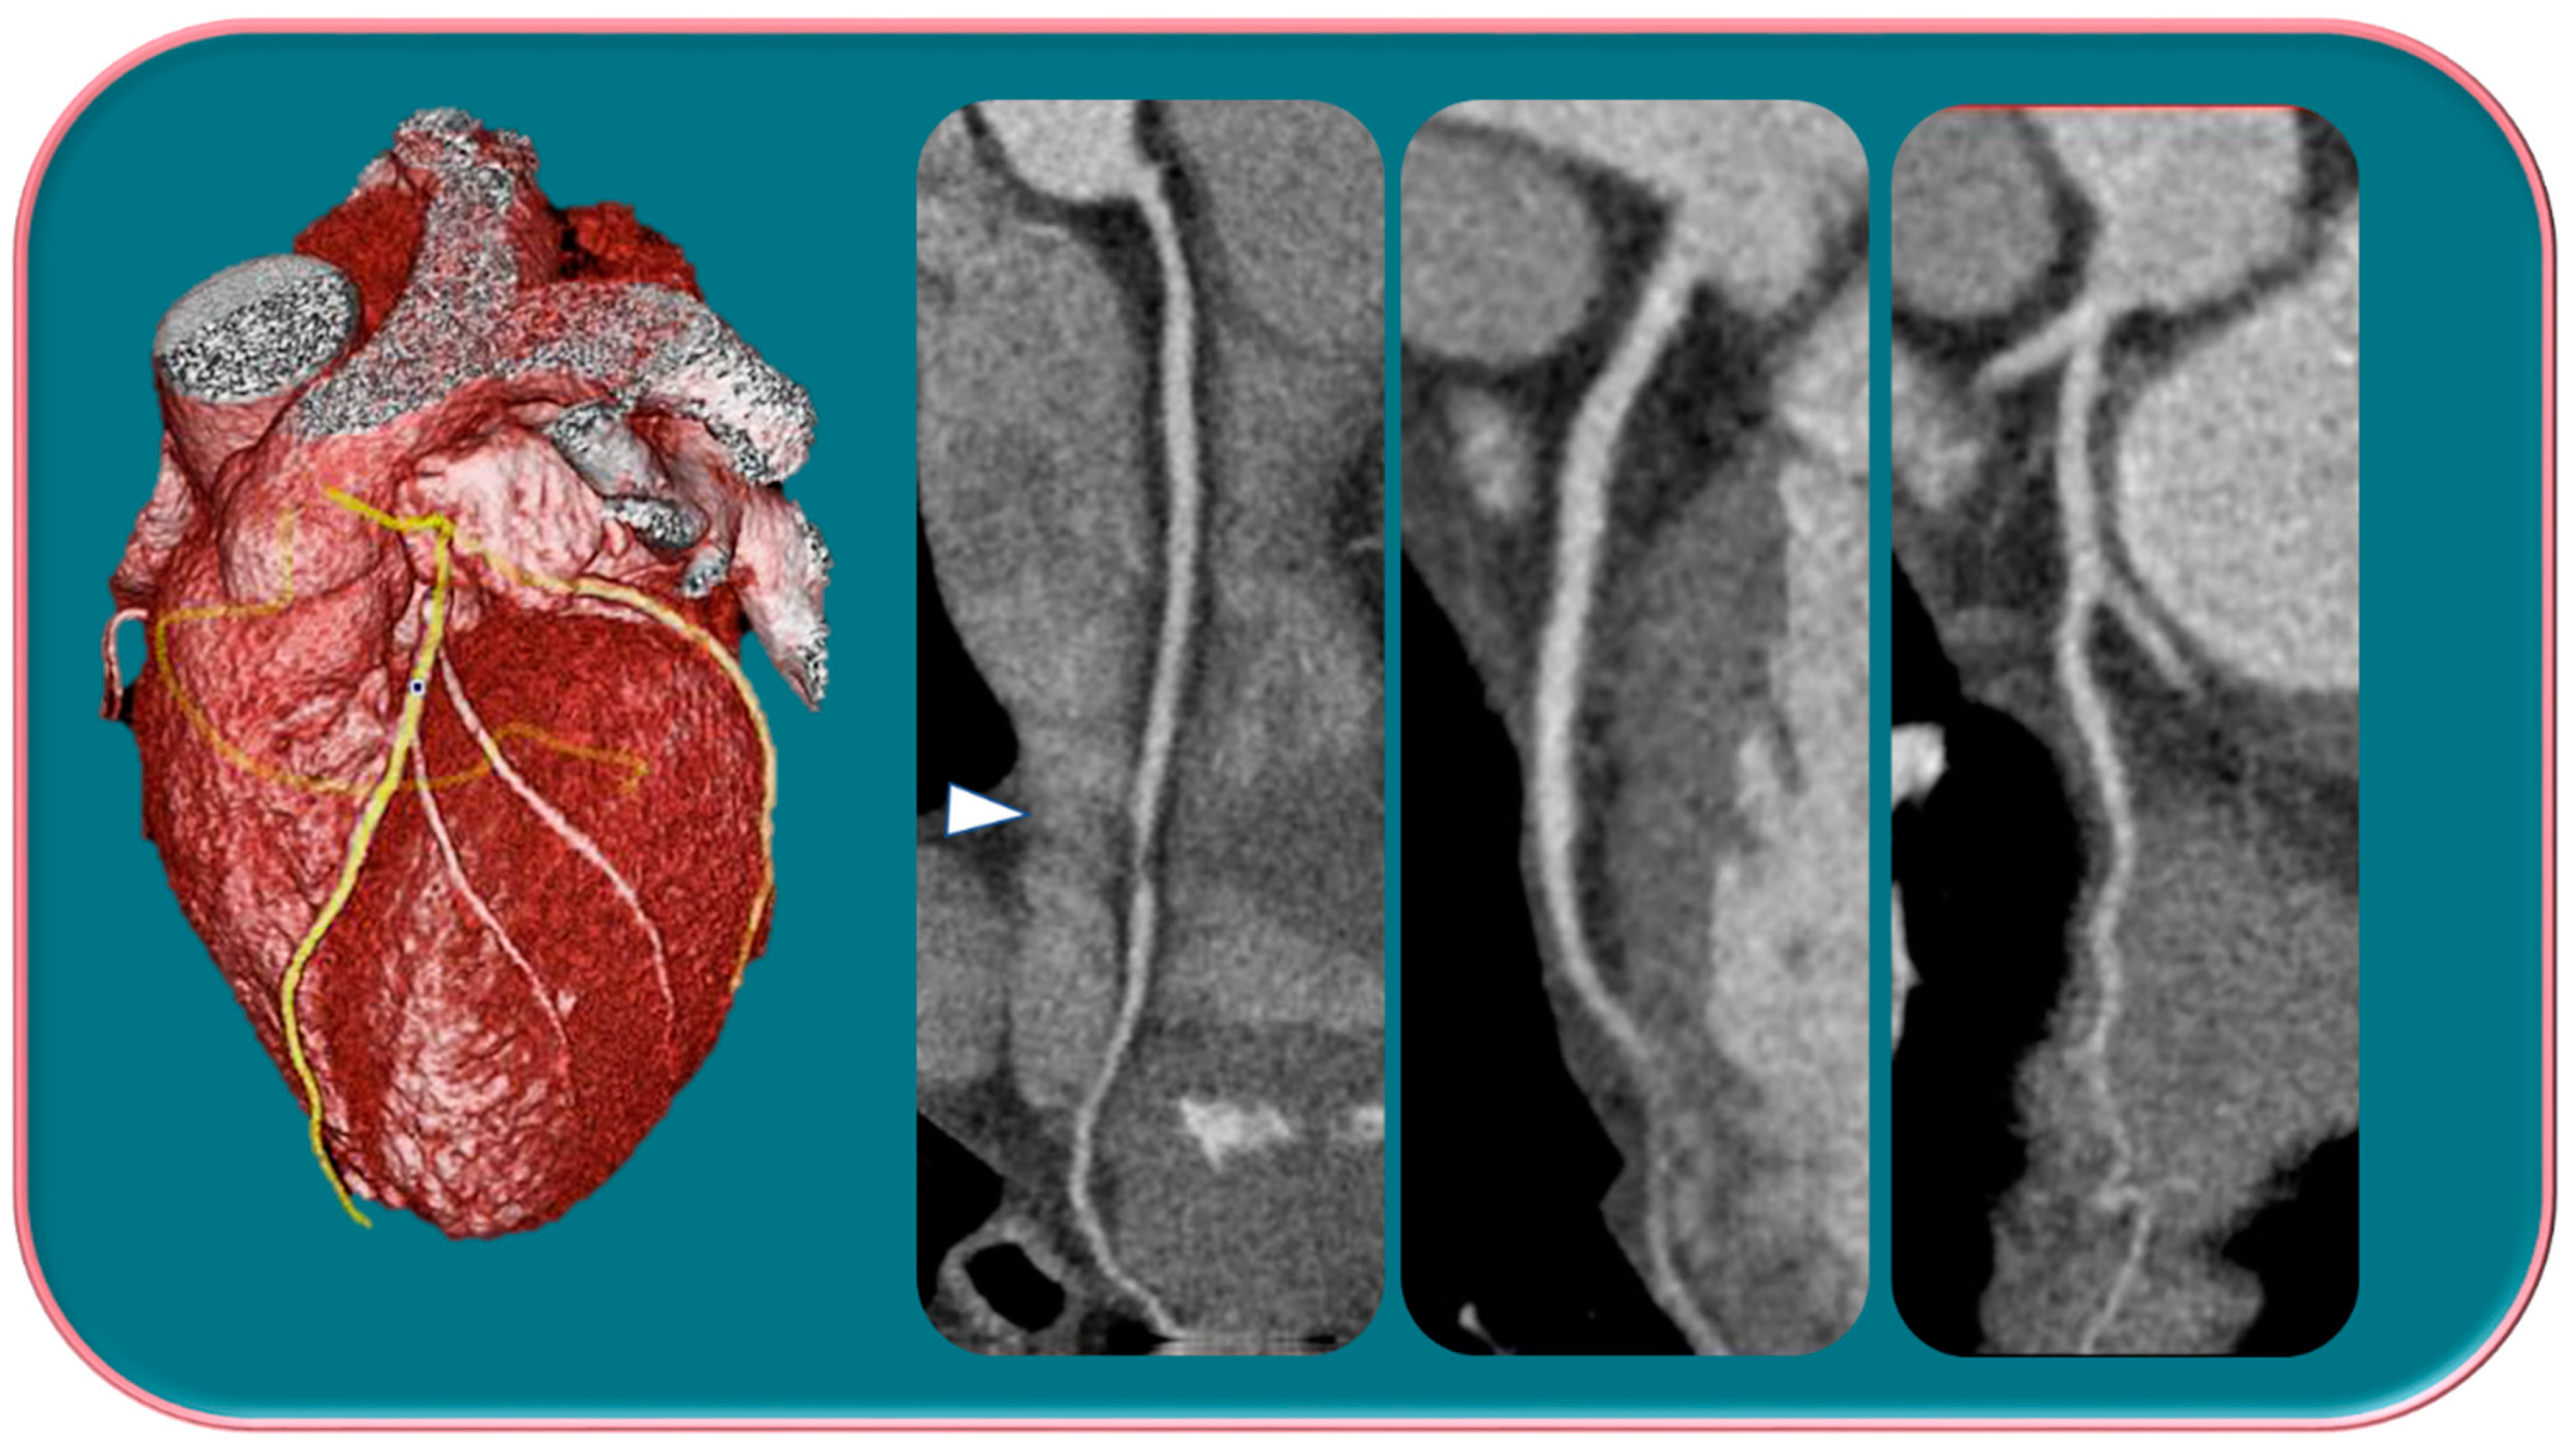

Kim et al. [29] in a study evaluated gender differences regarding the distribution and prevalence of CAC, its relationship to clinical risk factors, and the effect of a high calcium score (≥100) on subsequent initiation of medical therapy by evaluating a court of 542 individuals, of whom 279 were female and 263 were male. The data demonstrated an increasing CAC score with age, regardless of sex. However, women showed significantly lower CAC scores than men in the same age group. The lower CAC scores in women are likely in part indicative of the fact that women have a greater amount of non-calcifying plaque, so-called low-attenuation plaque, than men, indicating that lower CAC scores may actually be related to higher-risk plaque. However, there are also cases, although less frequent, of men with low-attenuation atheromasic plaque (Figure 1). Another interesting finding emerged from the correlation between CAC and clinical risk factors: for both sexes, age had a similar effect on CAC score (OR 1.11 and 1.12, respectively); however, in men, obesity showed a significant effect on CAC score (OR 2.16), while in women, smoking showed a significant effect on CAC score (OR 4.27). This result clearly demonstrated that the traditional clinical risk factors and which women, therefore, share with men actually have different clinical impact in the two genders. Finally, it was investigated how the CAC score result affected the further management of men vs. women with a CAC score ≥100 when adjusted for concurrent coronary CTA findings (moderate to severe lesions vs. non-obstructive lesions) in initiating aspirin and statin therapy [29].

Figure 1.

Male, 39-years-old, patients with history of dyslipidemia, type-1 obesity, and higher level of stress at work. The patient reported a non-anginal chest pain for which an ergometric ECG stress test was performed, and the results were negative. According to the Diamond–Forrester score, the patient was first categorized as a low pre-test probability risk of having CAD. To correctly rule-out CAD, the patients underwent CCTA examination, which showed a severe non-calcific plaque in the distal right coronary artery (white arrowhead).